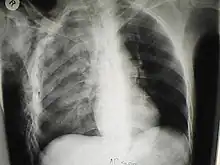

| A chest X-ray of a right sided pulmonary contusion associated with flail chest and subcutaneous emphysema | |